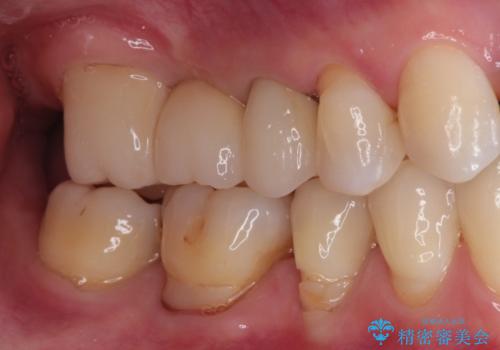

奥歯のオールセラミックブリッジ

オールセラミッククラウンのブリッジ修復にて治療を行っております。

十分に期間を治癒を待つことで審美性や清掃性の高い被せものを製作できます。